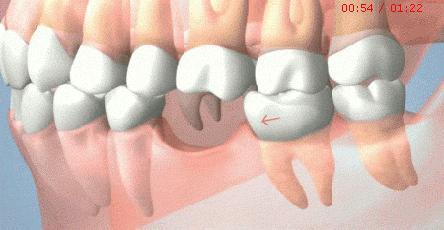

如果患者的牙齒咬合不平衡,使個別牙負擔過重,就會給這個牙造成創傷,引起局部的牙周病。因此,患者需要到醫院請牙科醫生對這顆牙進行調磨,以減輕它的負擔,免受創傷。